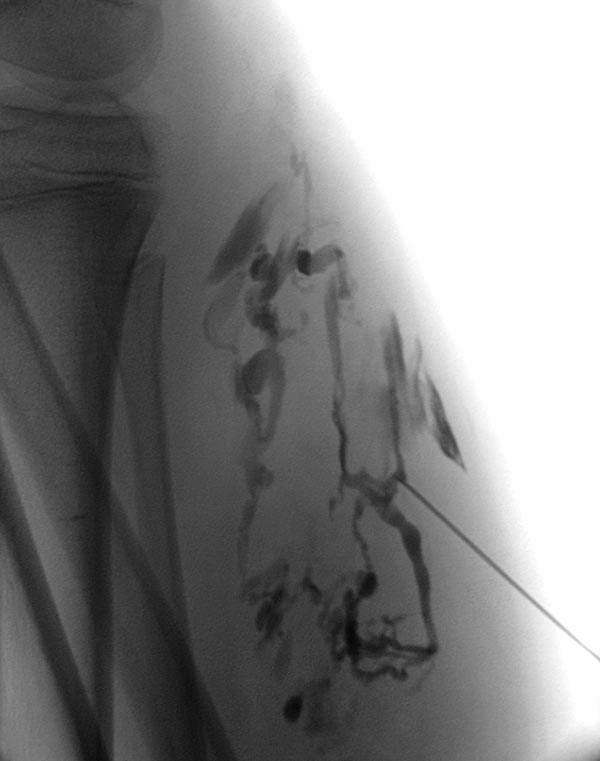

Phlebography after direct puncture of the venous malformation shows a large-lumen drainage vein communicating with the popliteal vein in the popliteal fossa. This must be occluded before sclerotherapy, otherwise the sclerosing agent could unintentionally dislocate through this communication and potentially cause thrombosis of the deep venous system of the leg and/or pulmonary embolism. In addition, there is an ongoing, increased risk of thromboembolism in this patient even outside of sclerotherapy, which can be significantly reduced by occlusion of the communication.

To occlude the vein, a large-lumen introducer sheath is first advanced via a guidewire. This sheath is used to insert the laser fiber and is advanced via the vein to the communication point in the popliteal fossa.

A laser fiber is advanced through this sheath for endovascular laser therapy. The heat of the laser beam causes massive irritation of the vein wall, which subsequently closes quickly. Thrombus formation immediately occurs around the laser tip.

After occlusion via laser fiber and contrast injection via the pulled-back introducer sheath, there is no more outflow of the contrast medium via the communicating vein. Thus the communication is successfully occluded. Only the venous malformation is still contrasted. This is now ready for sclerotherapy, as the sclerosing agent can no longer drain into the deep venous system of the leg.